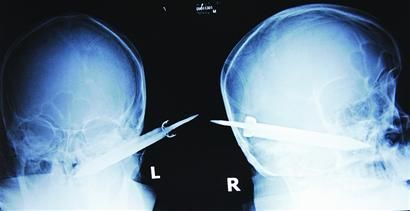

经过检查,医生说这把长有10厘米左右的刀,从右耳窝上前方直接刺进了鼻腔,离颌内大动脉很近,刀卡在了骨头中,要取出这把刀最怕大出血,万幸的是这把三棱刀并没有伤及大脑。

截至昨晚11时30分,患者头部刀经手术已取出,生命体征平稳。 (记者 芮潇潇)